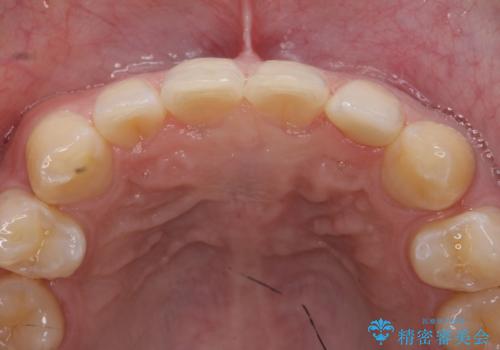

- 上顎前歯のすきっ歯が気になるといらっしゃった方の症例です。

上顎前歯のみの治療を希望されたので、部分矯正を行いました。

左上2の矮小歯はオールセラミッククラウンによる補綴を行いました。

今回用いたオールセラミッククラウンは、ジルコニアフレームという白い素材の上にセラミックを盛っているため審美性が非常に高いのが特徴です。

またジルコニアは人工ダイヤモンドの材料にも使われているほど高い強度を持っており、そのためオールセラミッククラウンは審美性だけでなく、奥歯やブリッジの補綴も可能とするクラウンです。